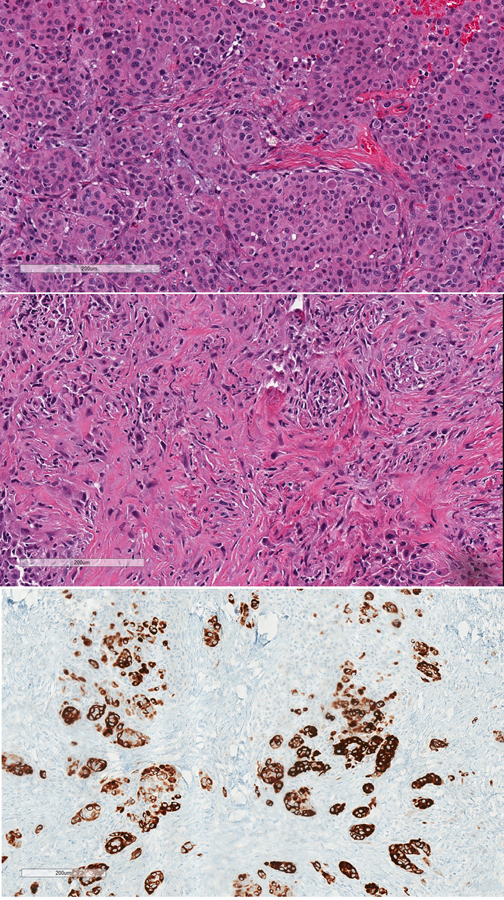

Nivolumab-induced peritonitis with peritoneal mesothelial hyperplasia mimicking metastatic mesothelioma

A 57-year-old man developed a mesothelial proliferation in the peritoneum, several months after he was diagnosed with biopsy-proven epithelioid mesothelioma of the pleura and having undergone several treatments with checkpoint inhibitor immunotherapy. The differential diagnosis was metastatic mesothelioma from the lung primary, versus a reactive process. A diagnosis of atypical mesothelial proliferation was made. Follow-up CT showed no evidence of abdominal disease 5 months later. The complication of serositis following checkpoint inhibitor therapy is reviewed, as well as the differential diagnosis between reactive mesothelial hyperplasia and epithelioid mesothelioma.